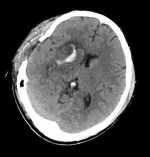

右側(cè)基底節(jié)區(qū)腦出血手術(shù)術(shù)式選擇及預(yù)防措施有哪些? 關(guān)鍵疾?。?a href="http://m.akellydesign.com/tags/so/腦出血-4-1.html" target="_blank">腦出血 現(xiàn)病史【一般資料】 男性,69歲, 【主訴】 左側(cè)肢體無力,伴言語含糊4小時 【現(xiàn)病史】患者入院前4小時前與他人爭吵后突發(fā)左側(cè)肢體無力,伴言語含糊,無意識喪失,無惡心嘔吐,無二便失禁,家屬急送我院。急診查體患者神智尚清,雙側(cè)瞳孔等大等圓,直徑2.5mm,光反好,左上肢肌力III級,左下肢肌力II級別,右側(cè)肢體肌力IV級。立即行頭顱CT發(fā)現(xiàn)右側(cè)基底節(jié)區(qū)腦出血,量約20ml。與家屬溝通病情后,予止血、改善循環(huán)、神經(jīng)保護(hù)及支持治療。后患者訴頭痛劇烈,左上肢肌力II級,左下肢肌力無主動活動。立即復(fù)查頭顱C...

周***超 | 醫(yī)師 外科 神經(jīng)外科 瀏覽:3545